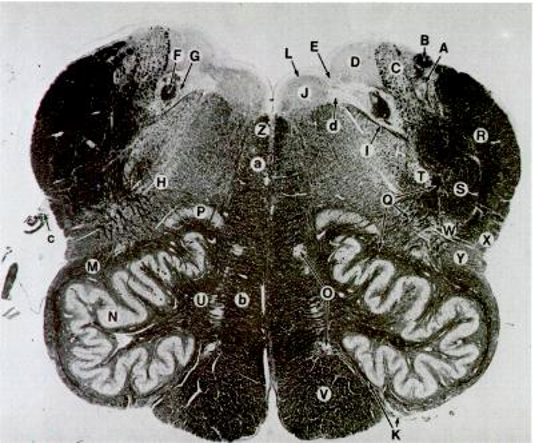

N

Inferior Olivary Nucleus

V

Pyramids

Y

Spinothalamic

G

Solitary Nucleus

H

Nucleus Ambiguus

b

Medial Leminiscus

C

CrN. X

J

CrN. XII

K